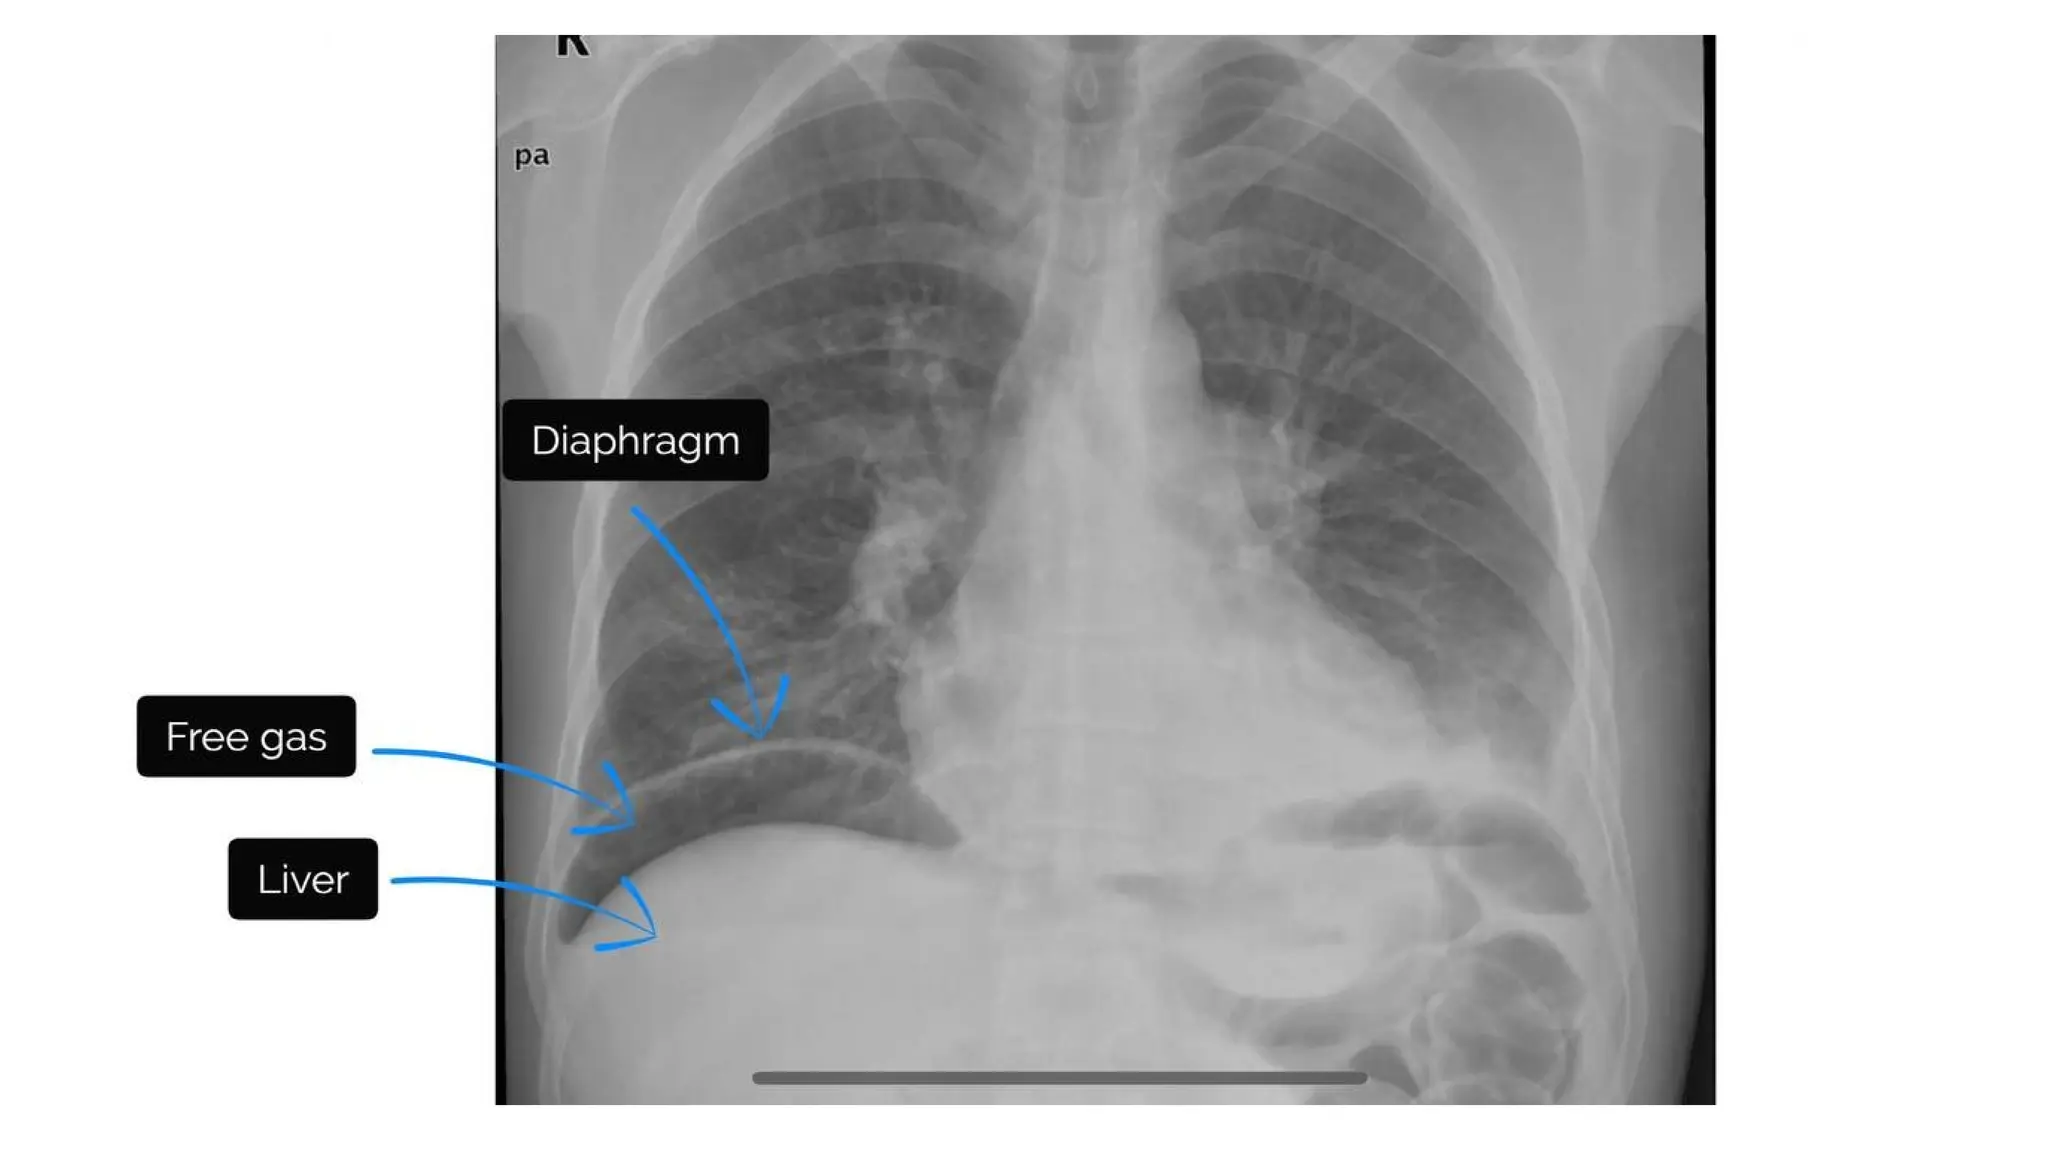

Hemidiaphragm

• Right hemidiaphragm higher than the left

due to presence of liver below

• Stomach sits under the left hemidiaphragm

and gastric bubble can be visualized

• Pneumoperitoneum= accumulation of air

under the diaphragm

• Results in the separation of the diaphragm

from liver.

• Often secondary to a bowel perforation